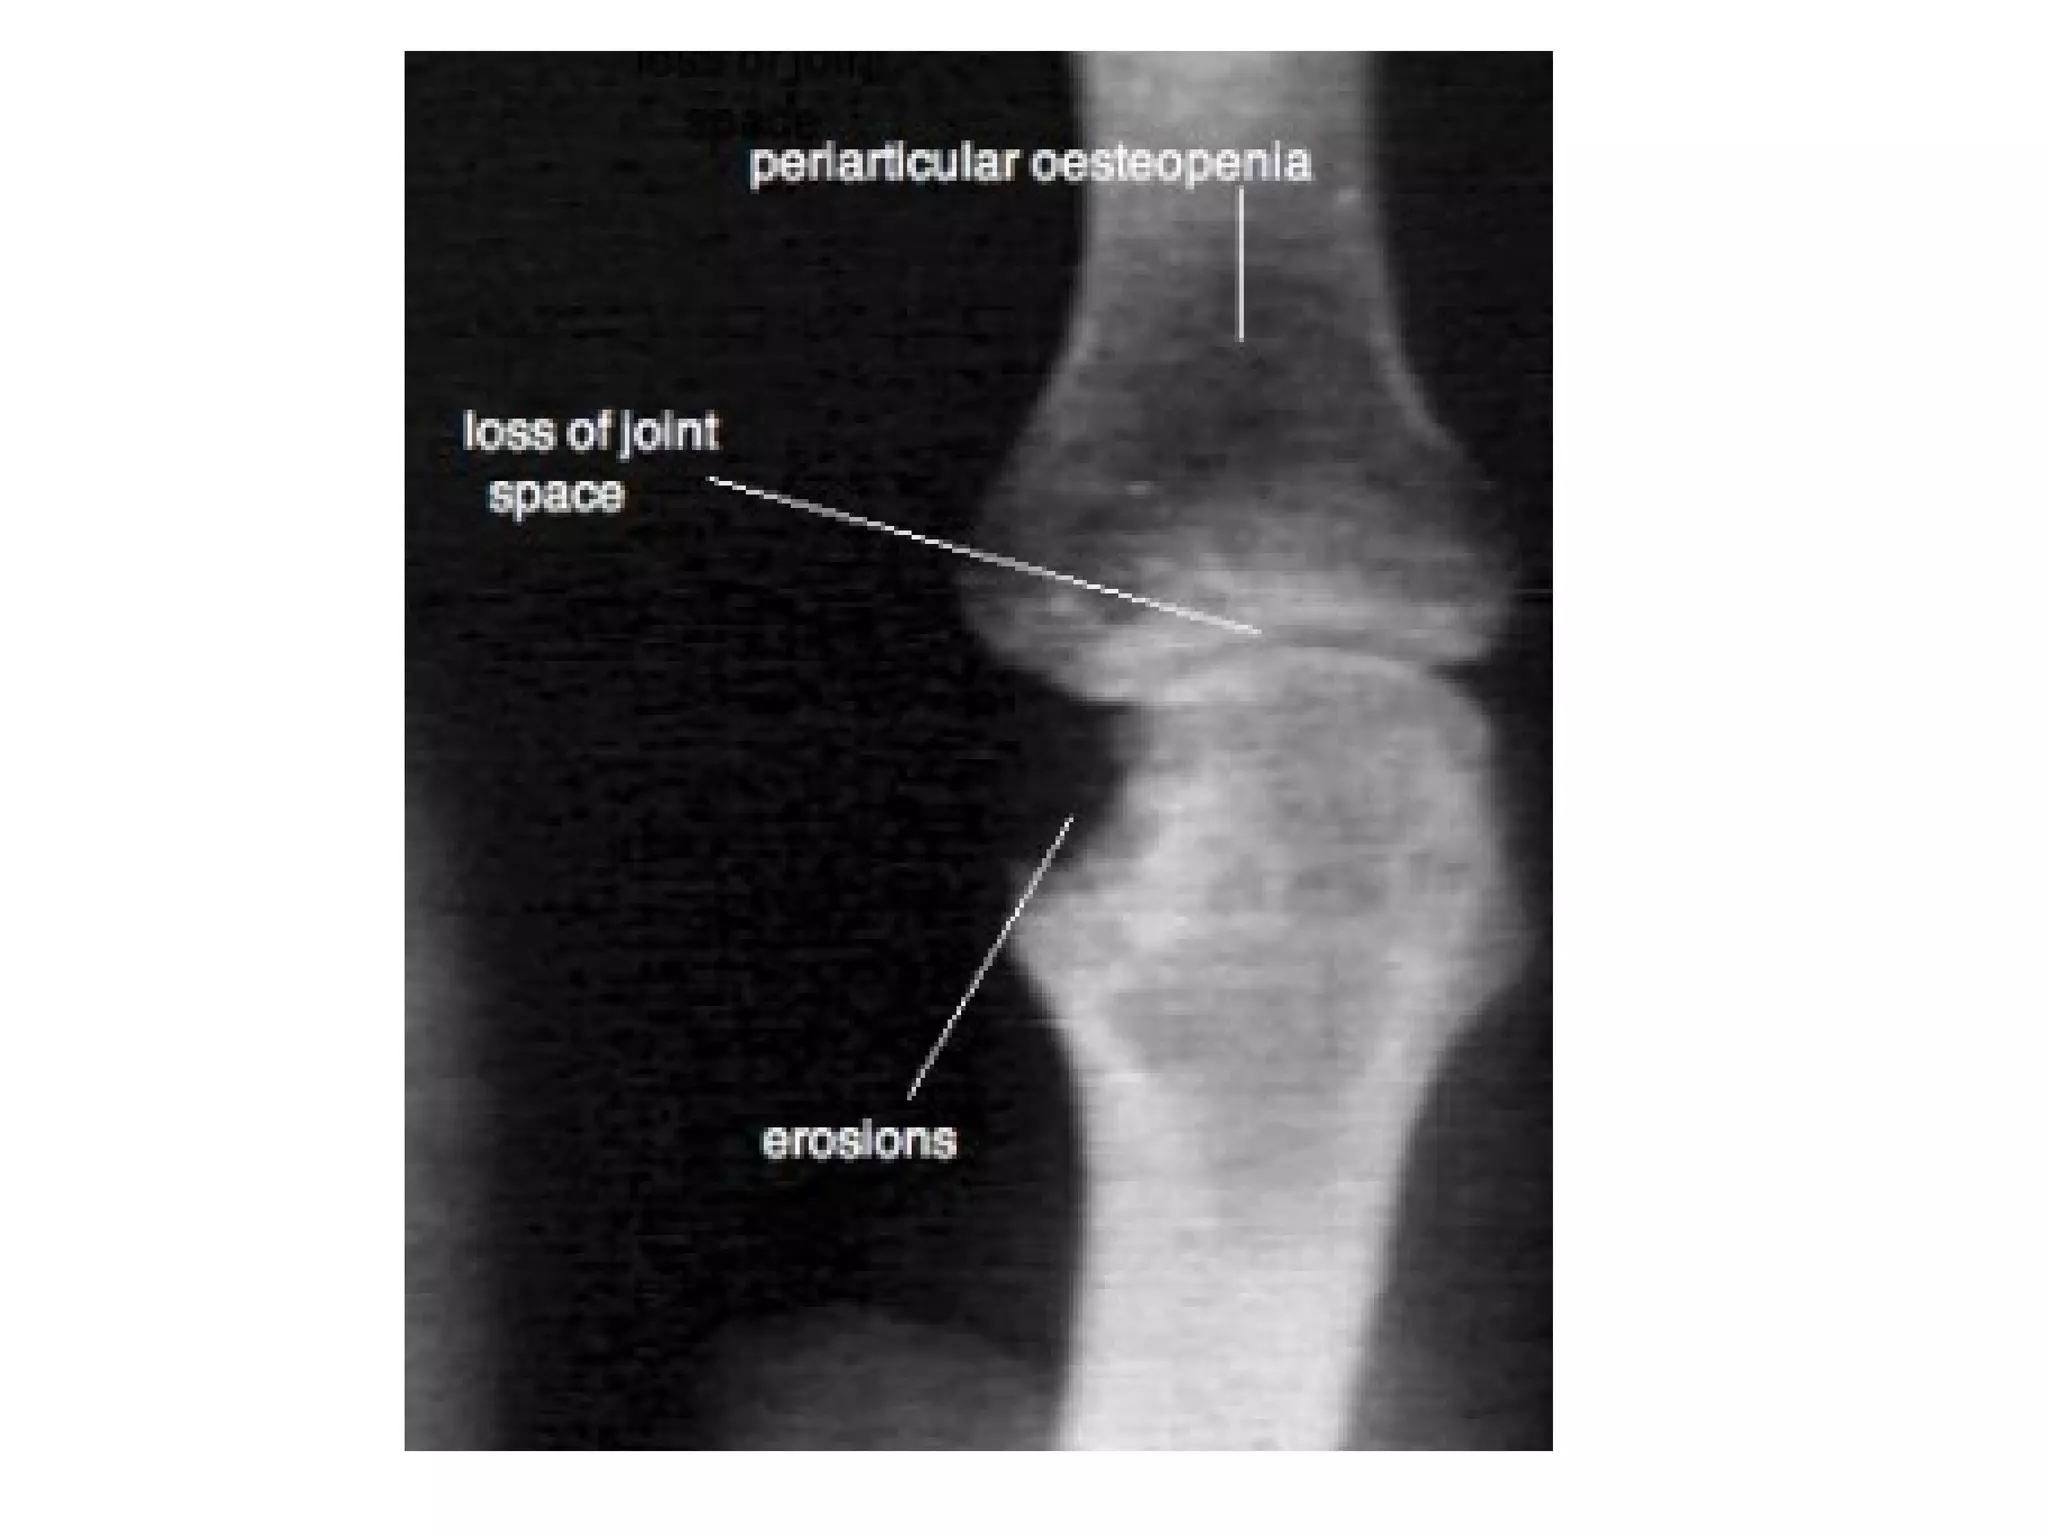

c) Radiographic Features :

(i) Skeletal Manifestations :

*Early :

1-Periarticular soft tissue swelling (edema ,

synovial congestion)

2-Periarticular osteopenia in symmetrical

distribution (hallmark), reflecting synovitis

& hyperemia